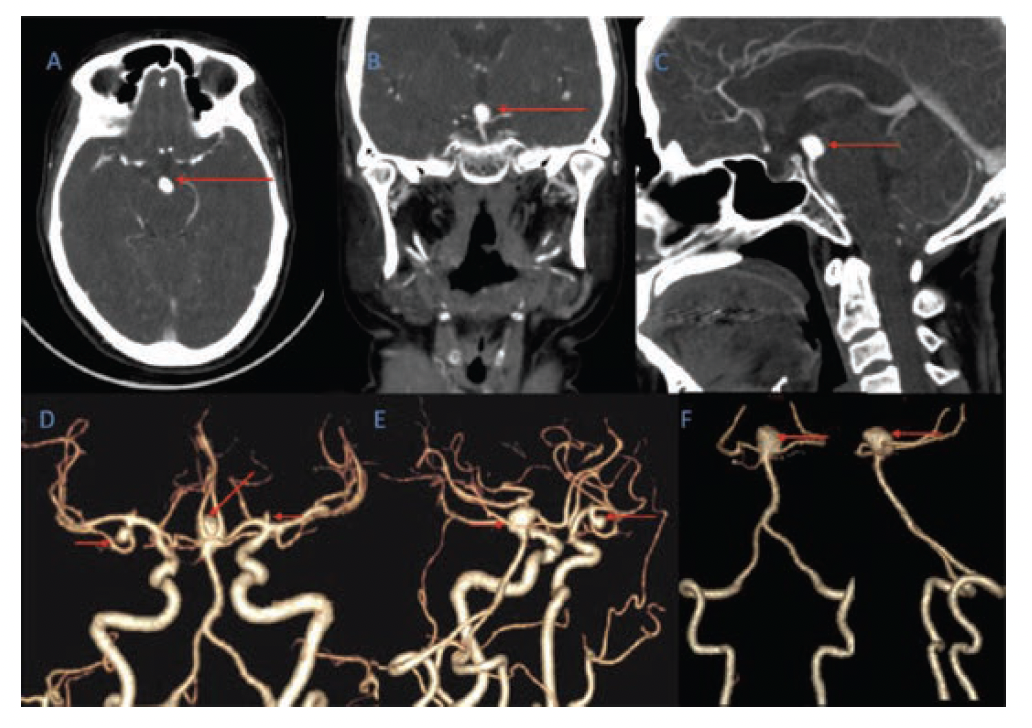

a Axial CT image showing SAH from a ruptured basilar apex aneurysm. B Coil Embolization Of Ruptured Basilar Artery Aneurysm the authors concluded that detachable platinum coil embolization was a promising treatment for ruptured basilar tip. given the wide use of endovascular coil embolization to treat intracranial aneurysms, it is important to establish recommendations, based on. patients and aneurysm characteristics. we retrospectively compared web embolization and coiling for the treatment of unruptured basilar tip aneurysms. . Coil Embolization Of Ruptured Basilar Artery Aneurysm.

Coil embolization towards the basilar artery aneurysm. (A, B) Complete Coil Embolization Of Ruptured Basilar Artery Aneurysm here, we report a child with a ruptured saccular basilar artery aneurysm that was successfully treated with coil embolization. given the wide use of endovascular coil embolization to treat intracranial aneurysms, it is important to establish recommendations, based on. patients and aneurysm characteristics. Between january 2012 and december 2023, 435 patients with intracranial aneurysms (316 unruptured and. Coil Embolization Of Ruptured Basilar Artery Aneurysm.

Figure 1 from Coil embolization for a ruptured posterior cerebral Coil Embolization Of Ruptured Basilar Artery Aneurysm unruptured baas accounted for 35/42 cases (83.3%), and the mean aneurysm diameter was 8.4 ± 5.4 mm. here, we report a child with a ruptured saccular basilar artery aneurysm that was successfully treated with coil embolization. Between january 2012 and december 2023, 435 patients with intracranial aneurysms (316 unruptured and 119. given the wide use of endovascular. Coil Embolization Of Ruptured Basilar Artery Aneurysm.